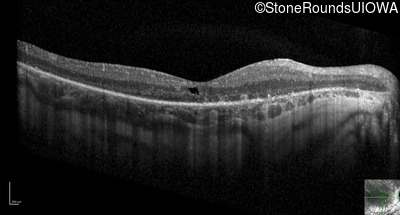

Optical Coherence Tomography - Right - 20/125 sc

Exemplar / OCT Stack